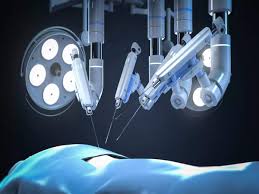

Introduction Robotic assisted surgery in Raipur is redefining modern medical …

Introduction Robotic assisted surgery in Raigarh is transforming modern healthcare …

Introduction Robotic assisted surgery in Narayanpur is a significant advancement …

Introduction Robotic assisted surgery is redefining modern healthcare by combining …